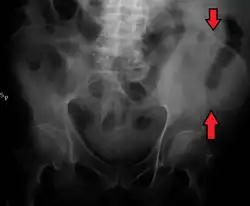

The crest of the ilium (or iliac crest) is the superior border of the wing of ilium and the superolateral margin of the greater pelvis.

The iliac crest stretches posteriorly from the anterior superior iliac spine (ASIS) to the posterior superior iliac spine (PSIS). Behind the ASIS, it divides into an outer and inner lip separated by the intermediate zone. The outer lip bulges laterally into the iliac tubercle.[1] Palpable in its entire length, the crest is convex superiorly but is sinuously curved, being concave inward in front, concave outward behind.[2]

The top of the iliac crests also marks the level of the fourth lumbar vertebral body (L4), above or below which lumbar puncture may be performed. Furthermore, said level is often referred to as the "intercristal line".